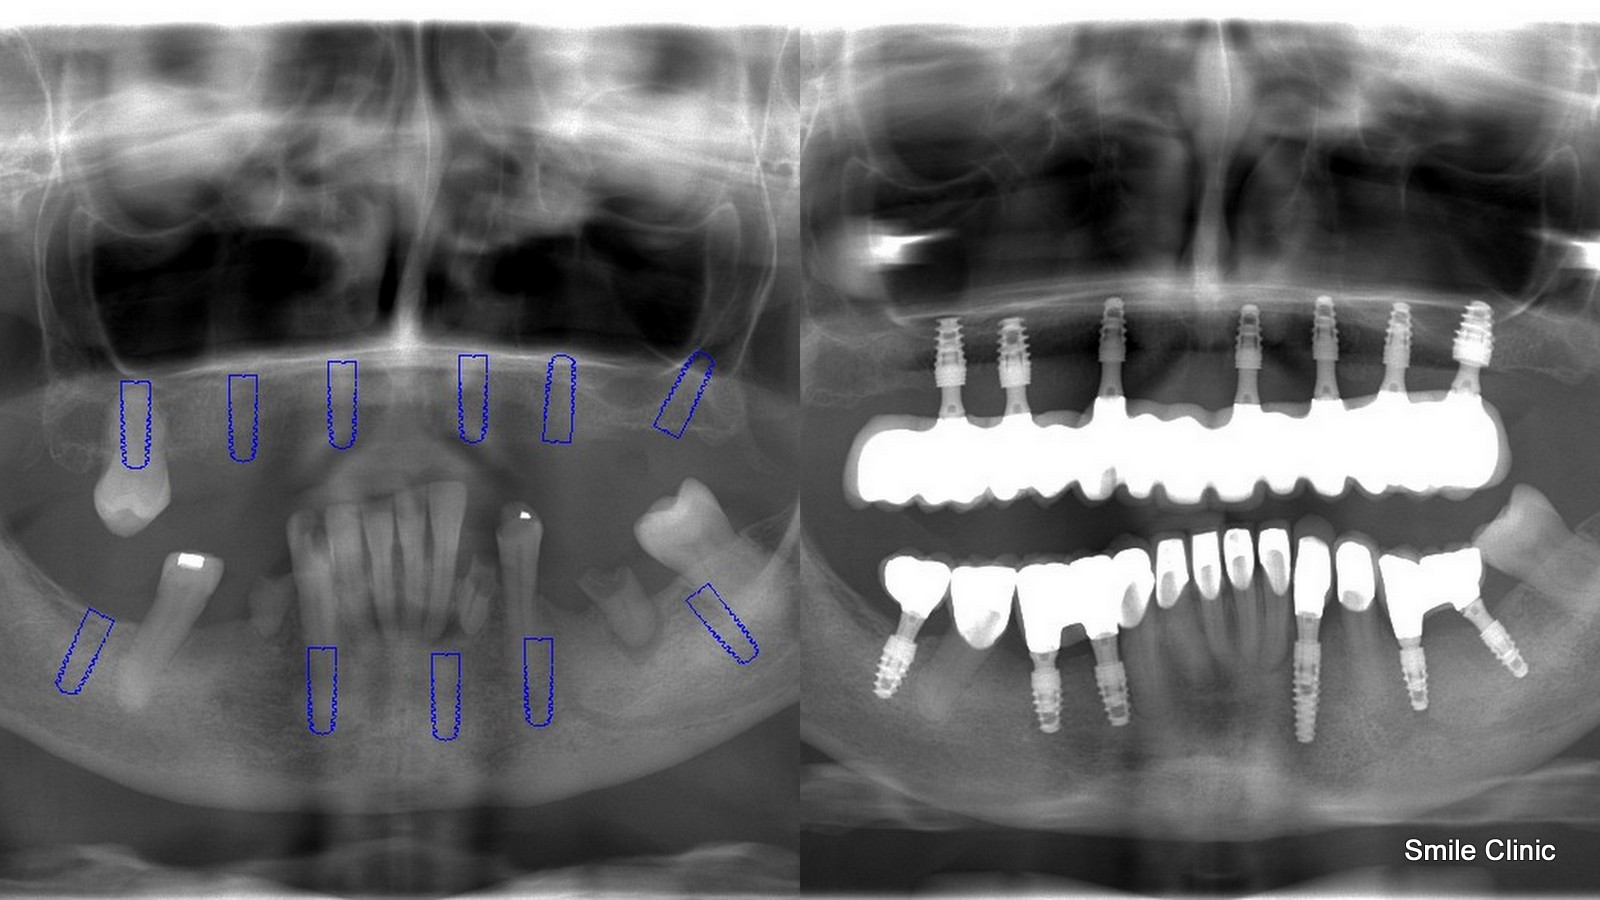

After over 100 email exchanges and a calming pill taken before treatment, in late November we finally got to begin our magic on Lynne’s smile. This involved placing 13 dental implants (7 to the upper jaw and 6 to the lower jaw) and then immediately replacing the denture and extracted teeth with a full semi-permanent bridge while the implants took 3-4 months to heal. (this specialty is only available in our clinic and included free with the overall treatment cost).

This amount of dental implants might sound like a lot, however especially in patients that have been using a denture (false teeth) for some time, the jawbone deteriorates and is not in the ideal condition to support a full jaw of teeth again. 2 visits later, 13 custom porcelain crowns in a bridge were created for both the upper and lower jaw – 26 in total as you can see from the x-ray here.